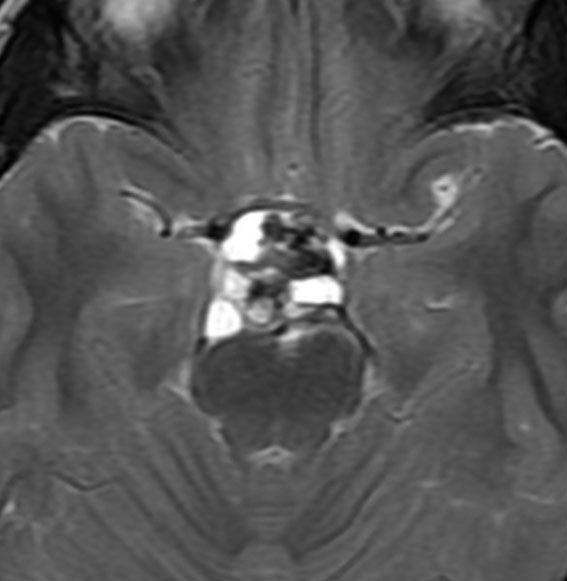

7歳の子が視力障害で発症しました。両耳側半盲という症状です。典型的な鞍隔膜下頭蓋咽頭腫です。ガドリニウム造影剤を入れないMRIでみえる,黄色い矢印の先の白い高信号は抗利尿ホルモンです。ですから下垂体機能もまだ残っていて,尿崩症はありません。視力障害が戻らないことがあるのでなるべく早く,経鼻的な手術で摘出した方がいいものです,簡単 o(^-^)o